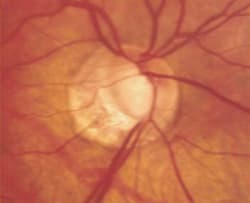

Fig. 1. Preperimetric glaucoma typically manifests as early

glaucomatous cupping of the optic nerve, thinning of the neuroretinal rim and baring of the circumlinear vessel. |

The large amount of RGC loss underlying detectable visual field defects in glaucoma means that our definition of early glaucoma should not be based solely on early visual field loss or high IOP. Only patients with preperimetric glaucoma -- identifiable optic disc abnormalities but no field loss -- should be considered to have early or mild glaucoma (See Figure 1). Once a visual field defect is detectable, the patient can be said to have moderate to severe glaucoma, depending on the degree of field loss (See Figure 2).